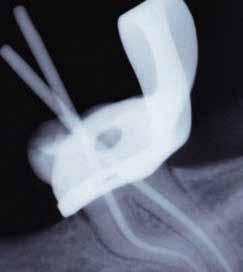

1. a–f ábrák: A cingulumon keresztül gömbfúróval kialakított hozzáférés a trepanációs kavitás labiális irányba történő túlzott mértékű kiterjesztését eredményezheti, és ez lényegesen növelheti a perforáció esélyét (a). A guttapercha átsejlik a lágyrészek alatt (b). Klinikailag igazolt perforáció (c). A preoperatív sagittális irányú CBCT-szeleten jól látható a labiális perforáció (d). Labiális irányú perforáció (fekete nyíl; e). A tényleges gyökércsatorna (piros nyíl; f).

2. a-b ábrák: A cingulumon keresztül gömbfúróval végzett trepanálás túlzott pericervikális dentin áldozattal, fordított tölcsér effektussal és perforációk kialakulásával járhat (fehér nyíl).

A frontfogakban történő hozzáférési nyílás kialakítása

A frontfogakban a hozzáférési nyílás kialakítását hagyományosan a fogak linguális vagy palatinális felszínén, a cingulumon keresztül egy gömbfúró segítségével kezdjük. A linguálisan elhelyezkedő kiemelkedés teljes eltávolítása, továbbá a pulpaszarvak teljes feltárása egy háromszög alakú hozzáférési nyílást eredményez. 7 Ezt a módszert a fogak esztétikai megjelenésének megőrzése érdekében fejlesztették ki. Ez azonban időnként a saját foganyag indokolatlan eltávolításával, a trepanációs kavitás labiális irányba történő túlzott kiterjesztésével, perforációval, valamint a fog kritikus helyen, a pericervikális dentin (PCD) területén történő meggyengítésével jár (1. a–f és 2. a-b ábrák). 19 Felmerült, hogy a pericervikális dentin rendkívül fontos szerepet játszik a rágóerő gyökerek irányába történő továbbításában, és elképzelhető, hogy a gyökérkezelt fogak hosszú távú megtartása szempontjából a legfontosabb tényező az ép pericervikális dentin megőrzése lehet. 20 A cingulumon keresztül történő hozzáférési nyílás

kialakítása során fennáll a fog labiális irányú perforációjának veszélye, mivel ilyenkor a foganyag elvételét labiális irányú fúrótartással kezdjük. Nemrégiben újragondolták a